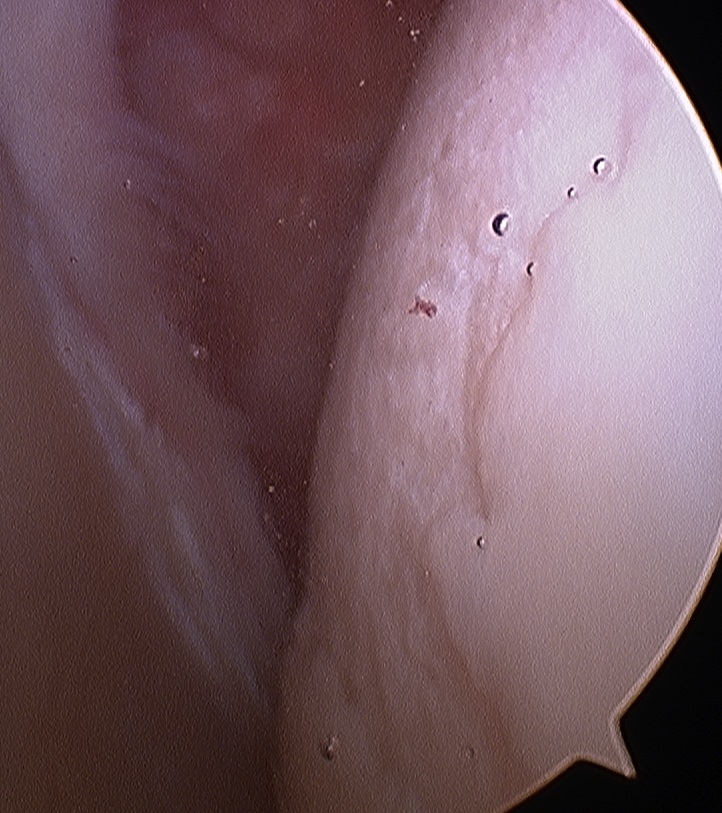

Rotator Interval - triangle of glenoid medial, biceps superior, subscapularis inferior

Humeral head cartilage

Glenoid cartilage

Labrum - anterior / inferior / posterior

Biceps tendon / insertion

Subscapularis

Glenohumeral ligaments